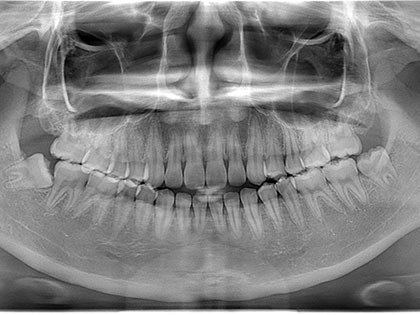

親知らず抜歯症例

親知らず抜歯症例1

親知らずを抜きたいとの事で来院、治療を希望された患者様の症例になります